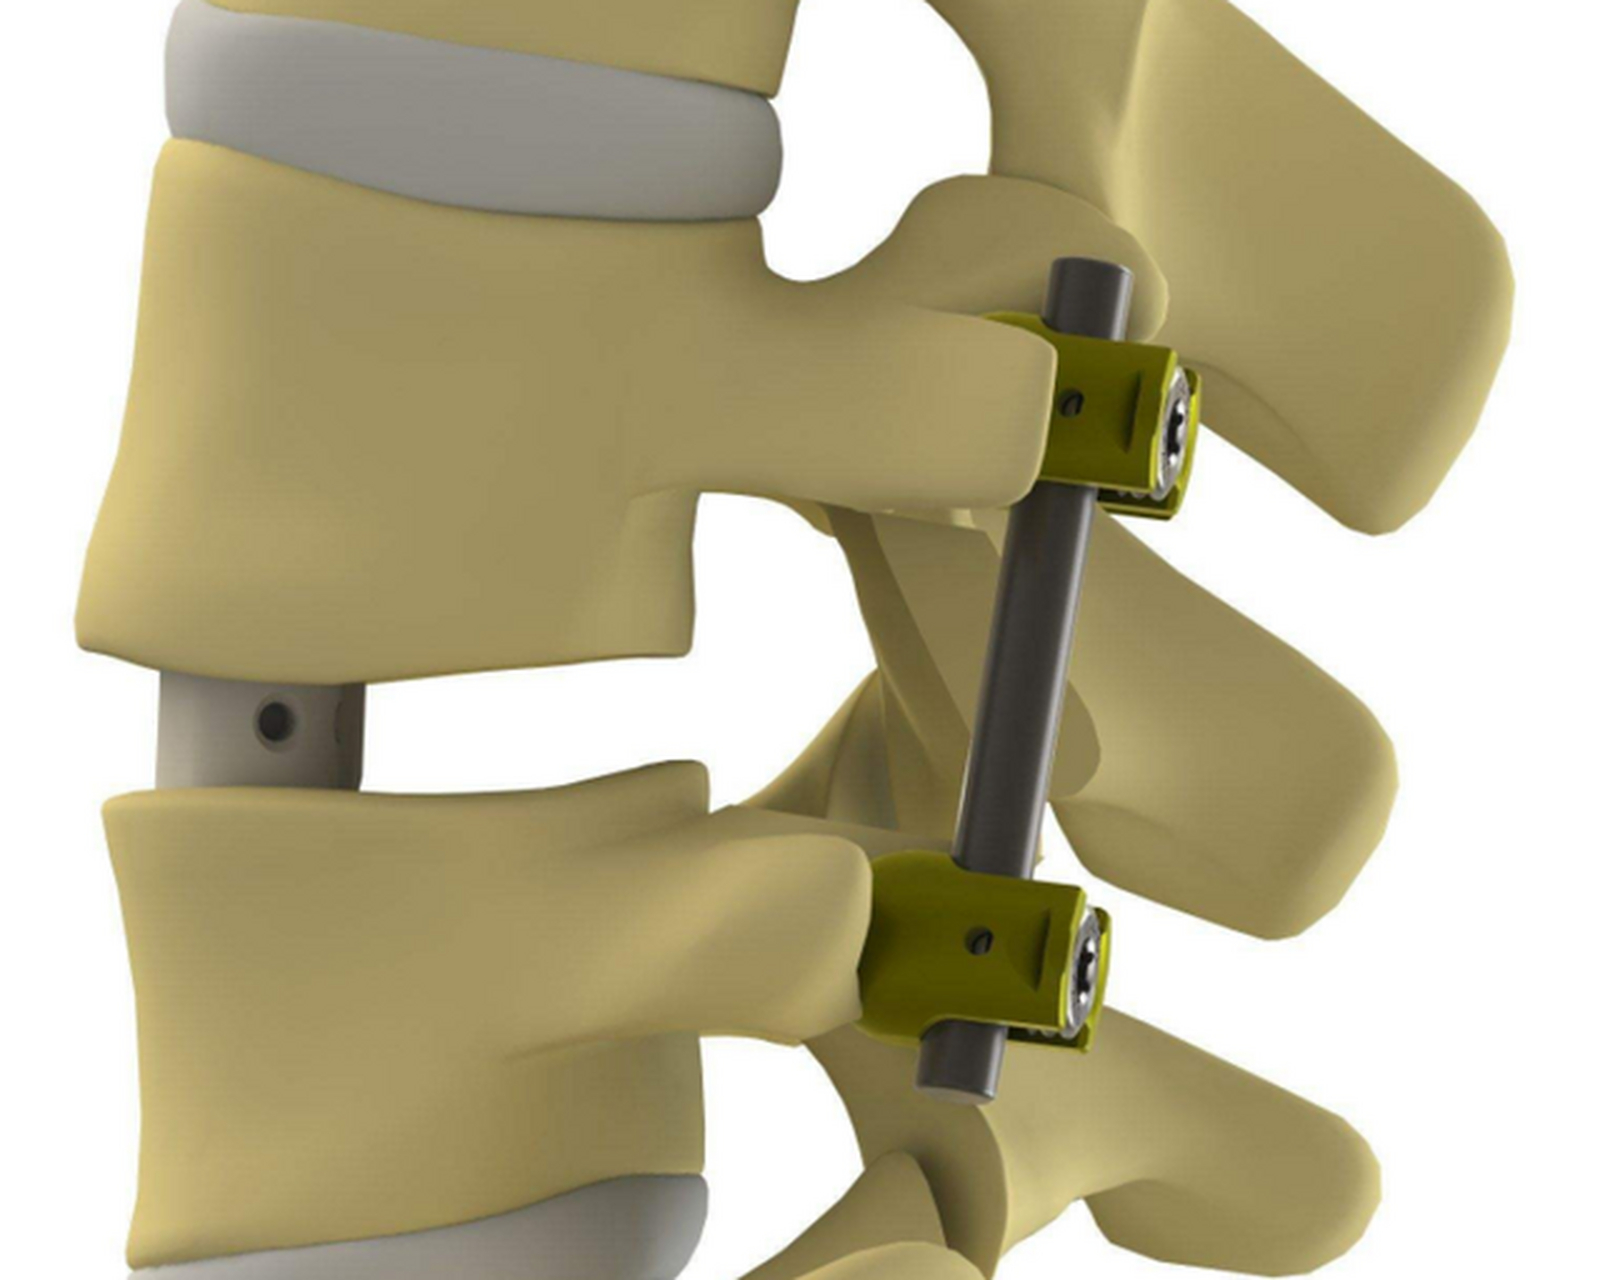

医学影像 原来腰椎钢钉是这样连接的